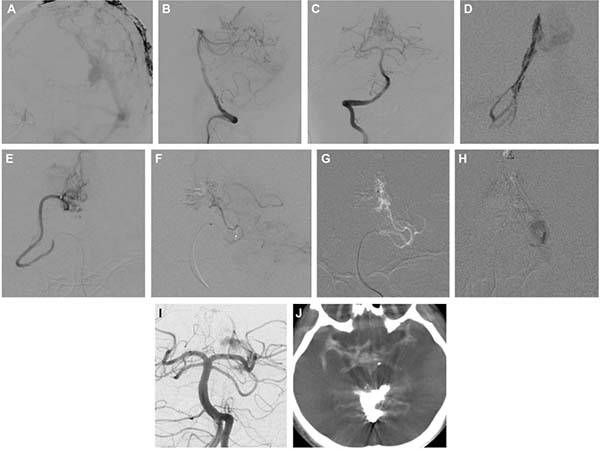

图1. A-D:对颈内动脉、颈外动脉及椎动脉行DSA显示一例由多支“纯”软脑膜动脉及硬脑膜动脉供血的Borden I型DAVF。供血动脉包括脑膜垂体干、大脑中动脉的“纯”软膜分支、枕动脉、脑膜中动脉、以及来自后循环的分支如大脑后动脉、小脑上动脉和小脑前下动脉。该患者有静脉窦支架植入病史,动静脉瘘正好位于原支架植入位置。此外,在后循环的软膜供血动脉中观察到与血流相关的动脉瘤。E-H:通过脑膜中动脉入路,在静脉途径球囊保护下使用Onyx完成瘘口的完全闭塞,未对任何PAS进行栓塞。I和J:完全栓塞后即刻行椎动脉造影,未见异常。K:静脉晚期显示患侧横窦-乙状窦仍保持通畅。L:术后患者保持意识清醒、反应良好,但返回病房后突发呼吸骤停。紧急头颅CT显示右侧颞叶出血,并伴有脑室内出血。